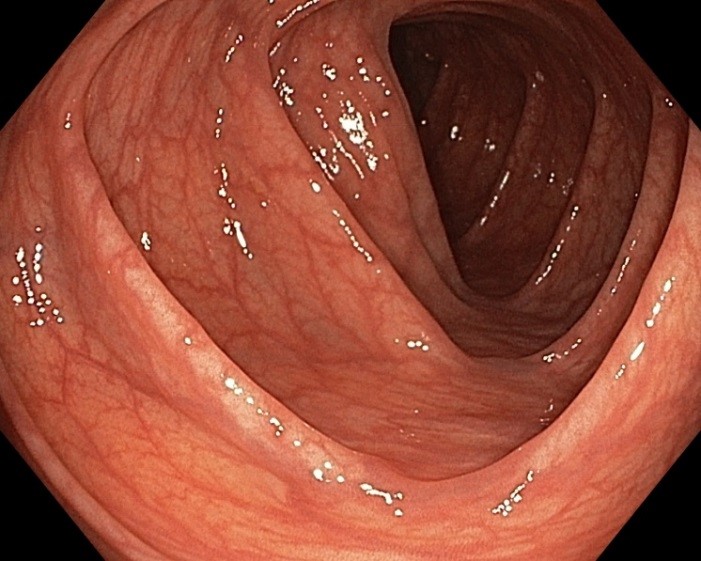

Колоноскопия является золотым стандартом диагностики и малоинвазивного лечения заболеваний толстой кишки, в том числе раннего рака и его предшественников (полипов). В целях профилактики рака толстой кишки колоноскопия показана всем после 40 лет, в среднем каждые 5 лет. Для достижения качественной подготовки толстой кишки к эндоскопическому исследованию и/или операции крайне важно строгое соблюдение всех этапов данных рекомендаций.

Некачественная подготовка толстой кишки резко снижает возможности эндоскопической диагностики (исследование будет не информативным!), что может потребовать повторной подготовки и проведения повторного исследования!

Соблюдение рекомендаций позволяет качественно провести исследование и выявить даже небольшие полипы

Соблюдение рекомендаций позволяет качественно провести исследование и выявить даже небольшие полипы